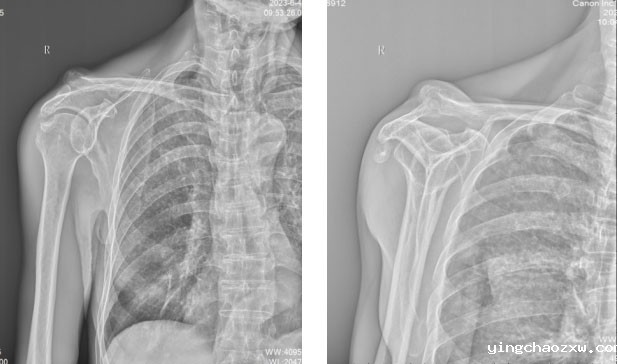

1.术前体格检查显示患者右侧肩功能严重受限,活动严重受限,需要依靠外力辅助才能活动

2.术前X片和CT提示严重的肩关节骨关节病。